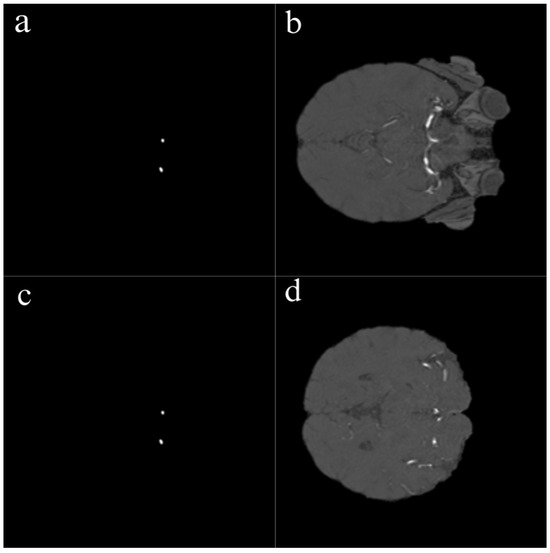

Magnetic resonance imaging (MRI) is a medical imaging technique used in radiology to generate pictures of the anatomy and the physiological processes inside the body. MRI scanners use strong magnetic fields, magnetic field gradients, and radio waves to form images of the organs in the body. The technology continually evolves as groundbreaking innovations and applications emerge. For example, some researchers use non-contrast MRI surveillance of craniopharyngiomas; some researchers found that by employing the spherical mean MRI technique, they can detect the IDH status in brain gliomas; and some researchers utilize generative artificial intelligence to transform grayscale MRI images into colour. This helps us to better understand multiple sclerosis, among other diseases.